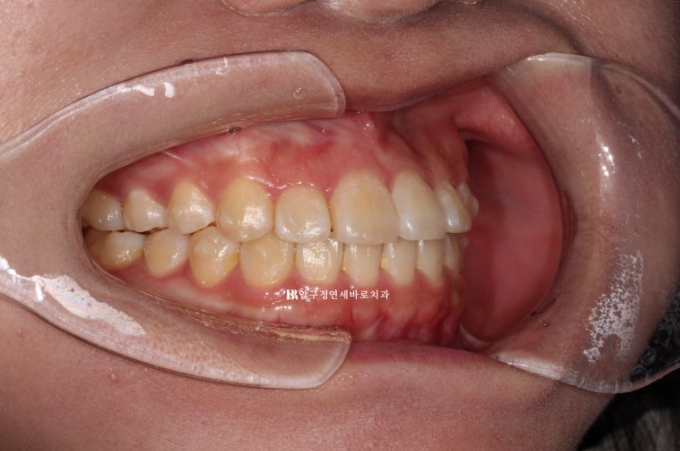

3개월에 걸쳐서 14개의 첫 세트 치료를 마무리 한 후 모습입니다.

앞니 뻗침이 많이 개선이 되었지만 앞니를 뒤로 조금 더 넣고 싶다는 환자분의 요구에 부응하여 추가장치 제작에 들어갑니다.

23.08